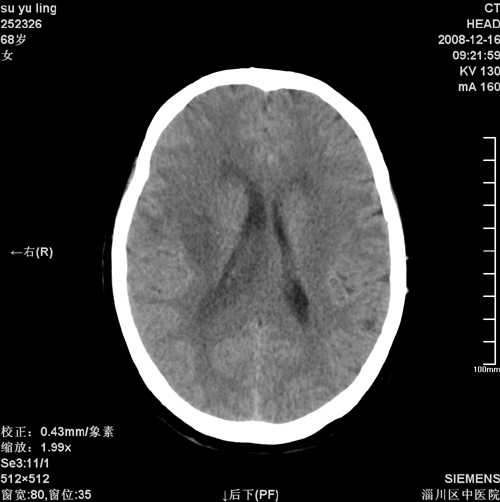

女,68岁,左侧肢体活动不利。

病灶比较均匀钙化,水肿明显,紧贴颅顶与大脑镰并跨越大脑镰----支持脑膜瘤

1)考虑镰旁脑膜瘤钙化。2)小脑萎缩。